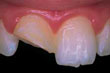

Εάν σπάσει κάποιο μικρό κομμάτι από ένα δόντι σας και δεν πονάτε, αποφασίστε μόνοι σας πότε και πώς θέλετε να αποκαταστήσετε το δόντι σας: το δόντι μπορεί να λειανθεί ή να «ξαναχτιστεί». Αυτό σημαίνει ότι ο οδοντίατρός σας μπορεί να χρησιμοποιήσει, επικαλύψεις από πορσελάνη, θήκες ή σφραγίσματα. Εάν χάσετε κομμάτι από σφράγισμα ή από κάποιο τεχνητό δόντι, το σφράγισμα ή το δόντι πρέπει να αντικατασταθούν.

Εάν κάποιο δόντι σας σπάσει ή ραγίσει πρέπει να αποκατασταθεί το συντομότερο δυνατό για να αποφύγετε επιδείνωση της ζημιάς. Στις περιπτώσεις αυτές μπορεί να χρειαστεί ενδοδοντική θεραπεία ή και εξαγωγή. Εάν το κάταγμα έχει κάνει ζημιά στο σμάλτο και στην οδοντίνη, τότε μάλλον είναι απαραίτητη η στεφάνη. Πρέπει να ξέρετε ότι τα κατάγματα δεν είναι πάντα ορατά ακόμα και σε ακτινογραφία. Το ράγισμα μπορεί να προκαλέσει πόνο όταν μασάτε και ευαισθησία στο ζεστό και στο κρύο, που με την πάροδο του χρόνου μπορεί να επιδεινώνεται.

![]() | σπασμένο μπροστινό δόντι |